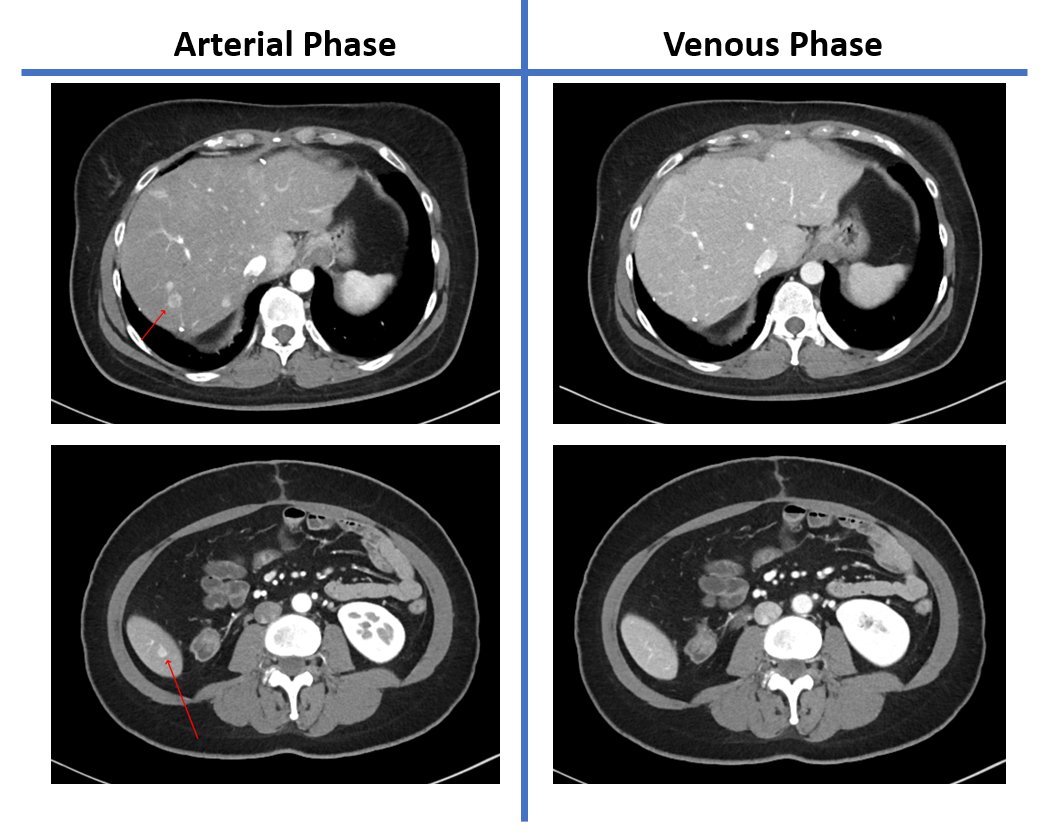

@hannarafa @AjayMorani @SanazJavadiMD @ginnylall @RSNA @MDAndersonNews Congrats on a great presentation. An honor to be a part of this team. @MDAndersonNews #oncsurgery

English

Hard work always pays off

🙌🎉Certificate of Merit award for

GIEE-1 Imaging Update For Hereditary Abdominopelvic Neuroendocrine Tumors. Thank you all for your fantastic work. It has been a pleasure working with such a highly qualified and competent team #rsna21 #radiology #rsna